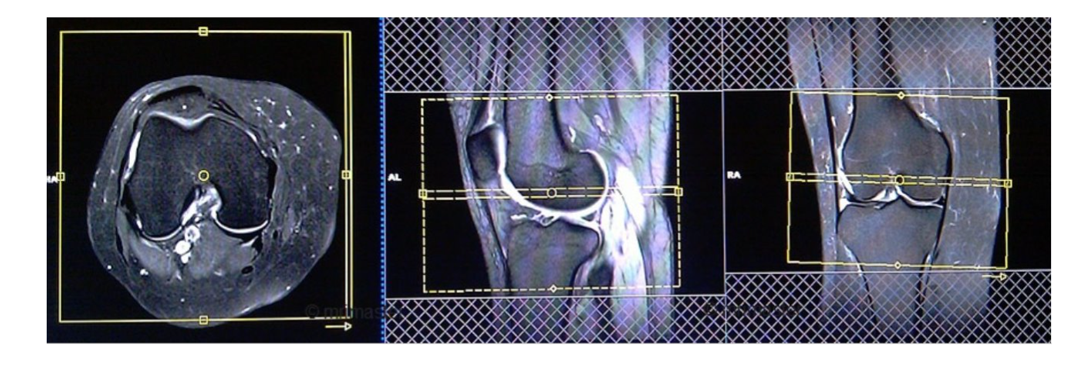

AXIAL

CORONAL

SAGITTAL